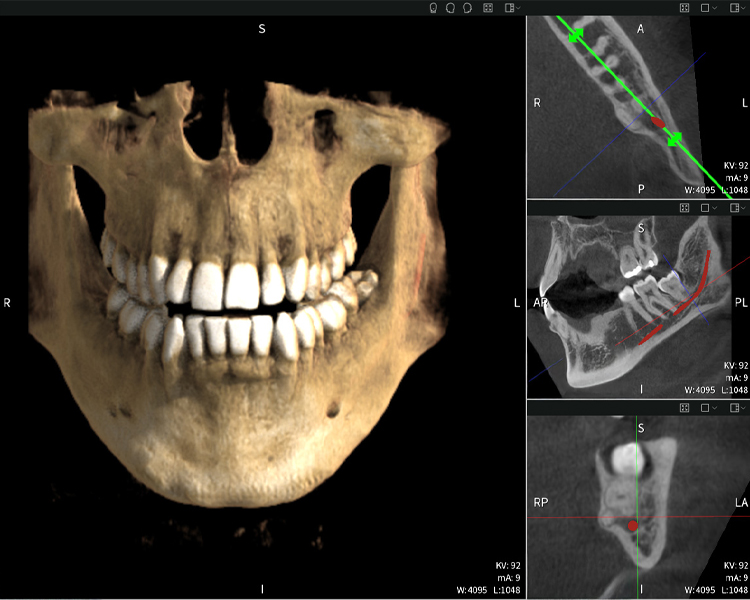

Abbildung b: Bildgebungsergebnisse von Seethrough Max vor einem schwarzen Hintergrund.

Abbildung b

Abbildungen b–d zeigen verschiedene Ansichten einer 3D-Rekonstruktion des Unterkiefers und bieten eine umfassende Übersicht über die Anatomie des Unterkiefers, die Lage der Nerven im Verhältnis zu den Zähnen und ermöglichen die Beurteilung der Zahnsymmetrie und Ausrichtung.